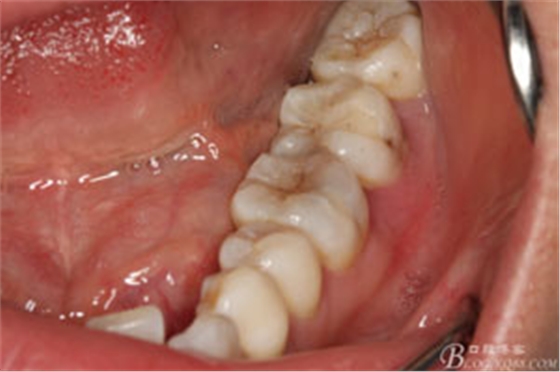

圖2.37牙冠基本完好,松動Ⅰ度。合面有一開髓孔被棉球覆蓋,頰側(cè)牙齦輕度紅腫。